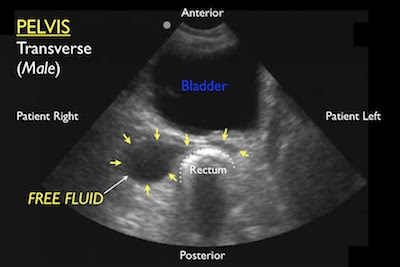

- Component: FAST abdominal views

- Probe: Phased array probe (3.5 – 5 MHz)

- Location: Hepatorenal recess, Splenorenal recess, and bladder

- Finding: Internal blood loss